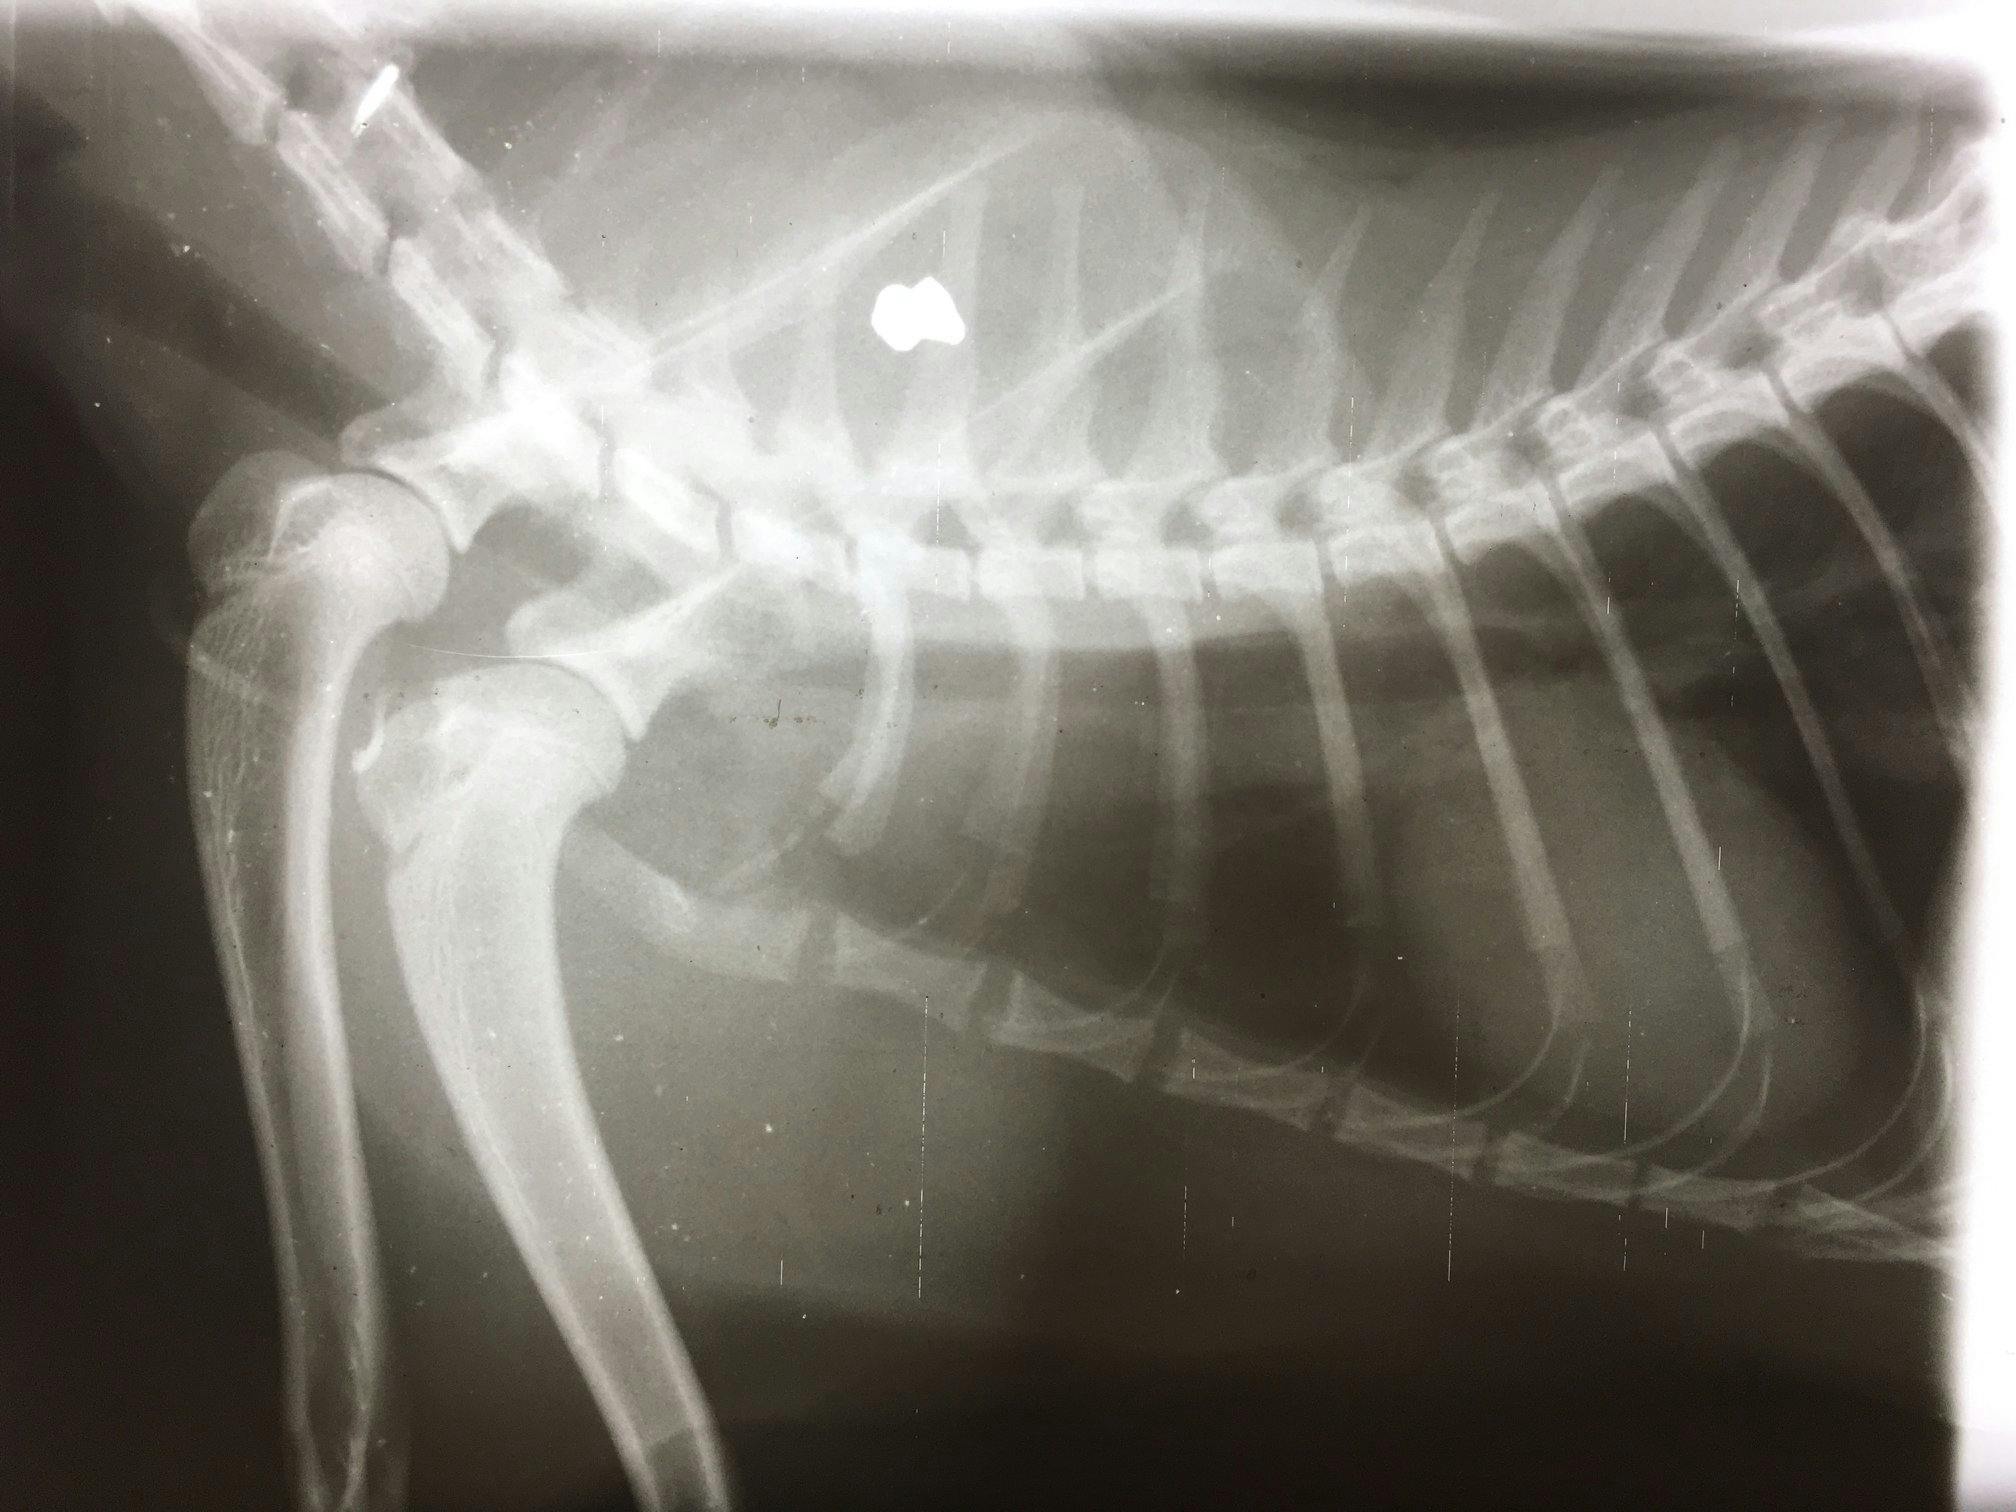

- Kattens ejer troede den var blevet bidt, men nej - på røntgenbilledet, som vi har vedhæftet, ser man tydeligt et hagl mellem rygraden og skulderbladet. Efter en lang operation ligger den søde kat nu på opvågningsstuen, skriver Greve Dyrehospital på deres Facebook-side.

- Haglet lå helt inde ved ryggraden, så det gør situationen lidt anderledes. Men heldigt nok har haglene ramt noget knoglefrembrud, som har 'bouncet' de her fragmenter rundt, så de ikke er gået direkte igennem. Men den havde meget ondt, siger dyrelægen til den lokale tv-station.

- Det er sket inden for de sidste par måneder, og det er alle blevet skudt med et kaliber 45 haglgevær, kan vi se på de hagl, de har haft i kroppen, siger han videre.